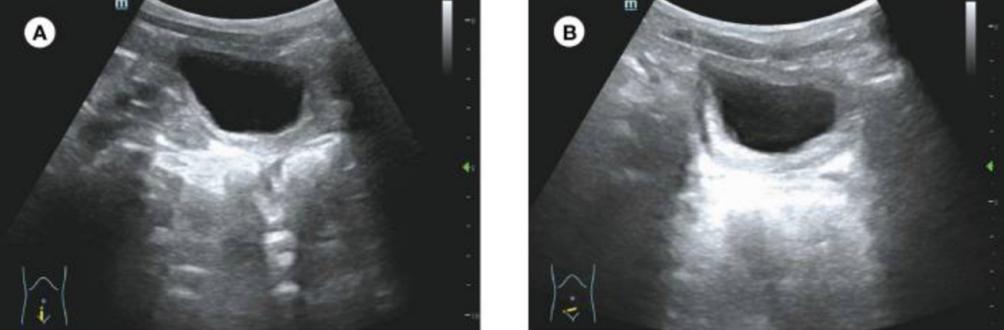

有趣的是,术后病理显示,组织表面覆盖着多层鳞状上皮,薄壁组织中发现大量纤维结缔组织和血管网腔隙。此外,还可以看到慢性炎症细胞、神经组织和平滑肌束(图2)。这表明该组织是海绵体。免疫组化显示CD31(+)、CD34(+),CK-pan(+)和F-VIII(+)。最终诊断为膀胱海绵体异位。患者在手术后5天出院。术后10个月,超声显示膀胱无明显异常(图3),患者无尿频症状。目前,该患者仍在接受随访。

图3 患者手术后10个月的超声检查。(A,B)超声检查未发现膀胱有明显异常